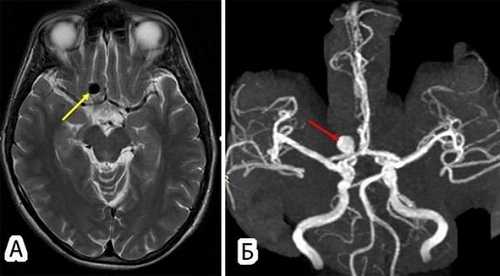

Субарахноидальная гематома на снимках МР-ангиографии

Артерио-венозные мальформации имеют вид аномальных соединений, переплетений кровеносных сосудов. В месте локализации патологии отмечают нарушение гемодинамики, изменение церебральных структур.